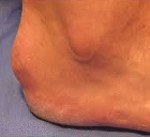

Обычно заболевание развивается в пубертатном возрасте, хотя возможно и более раннее начало – описаны случаи болезни Шинца у пациентов 7-8 лет. Начинается исподволь. Возможны как острые, так и постепенно усиливающиеся боли в пятке. Болевой синдром возникает преимущественно после нагрузки (бега, продолжительной ходьбы, прыжков). В области пяточного бугра появляется видимая припухлость, однако признаки воспаления (гиперемия, характерное давление, жжение или распирание) отсутствуют. Отличительными признаками болевого синдрома при болезни Шинца является появление болей при вертикальном положении тела через несколько минут или сразу после опоры на пятку, а также отсутствие болей в ночное время и в покое.

Болевой синдром появляется после физической нагрузки, даже непродолжительный отдых помогает уменьшить боль. Может появиться небольшая, едва заметная припухлость в месте крепления сухожилия к пяточной кости, остальных симптомов воспаления (краснота, отечность, пульсирующее неприятное ощущение) чаще всего нет.

Отличительной особенностью недуга является дискомфорт при опоре на пятку в вертикальном положении. Неприятные ощущения не появляются ночью и при отдыхе.

По фото болезни Шинца видно, что нога становится больше, явно заметна деформация пяточной кости.

Деформация пяточной кости при болезни Шинца